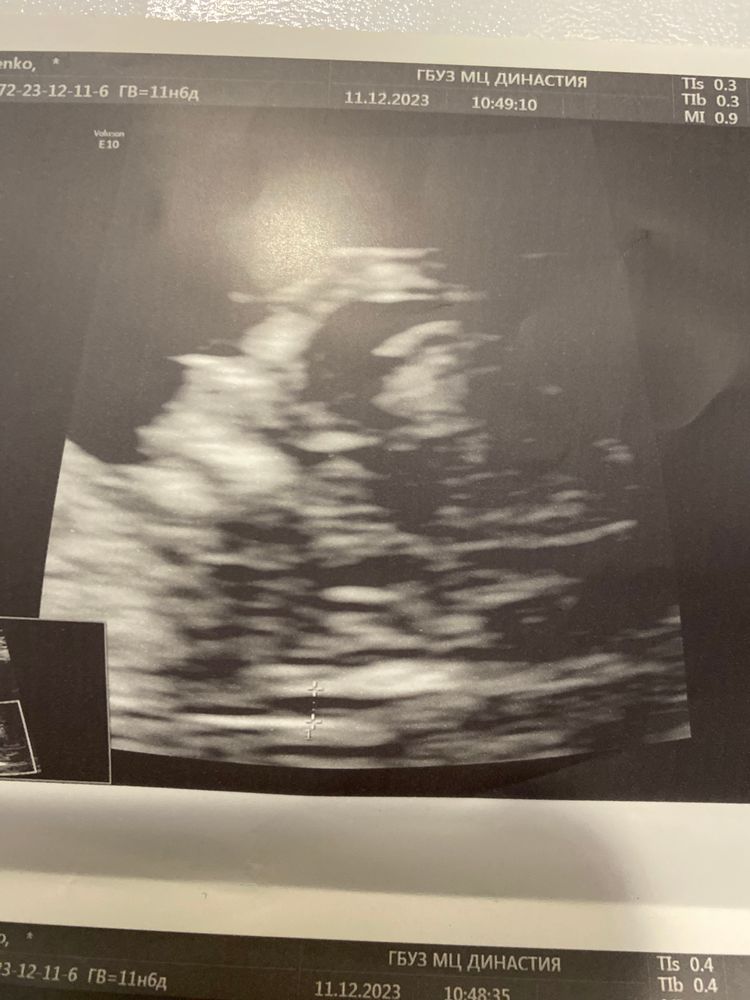

Изображение

Сложно сказать? А мы с узи! 🤰💞